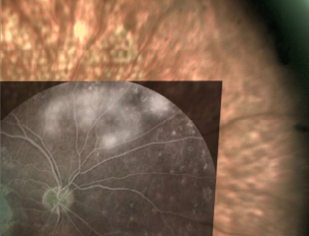

Was ist eine navigierte Lasertherapie?

Die navigierte Lasertherapie kombiniert die retinale Bildgebung mit einem therapeutischen Netzhautlaser. Unser NAVILAS® System der neuesten Generation führt die Bilder der Netzhautangiographie/der optischen Kohärenztomographie mit dem Behandlungsplan zusammen. Hieraus resultiert eine hohe Präzision und Sicherheit der Behandlung sowie, durch eine reduzierte Blendung bei Behandlung unter Infrarot-Licht, eine geringere Belastung der Patienten. Durch eine spezielle Einstellung des Lasers (Pulsserien) wird eine netzhautschonende Behandlung bei Makulaerkrankungen möglich.

Planung der Laser-behandlung:

1 - mit Einführung der Daten von der Netzhautangiographie

2 - Digitale Kontrolle der Netzhaut und

3 - Dokumentation sofort nach der Behandlung.